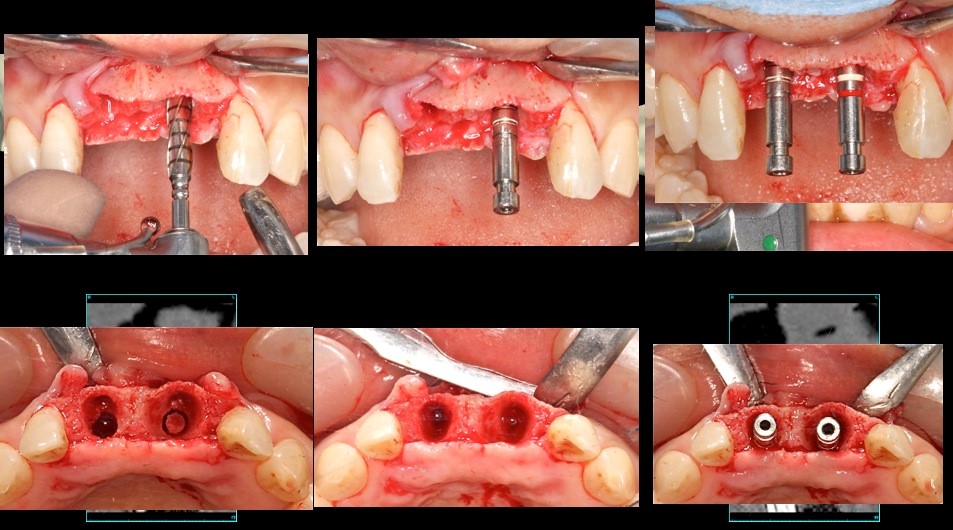

上顎前歯部フライスドリルで形成(直径3.5㎜)埋入インプラントは10㎜の計画であるがフライスドリルでは14㎜まで骨採取のために形成する 深度ゲージで深度確認 形成部位に骨尖を確認することができる(左上1)(右上1はすでに骨採取後)

クリッケラー先生考案の骨採取の鉗子にて骨尖採取

インプラント埋入 抜歯窩とインプラントに空隙があることがわかる

この部位に中切歯2本分の骨尖を砕いて隙間に填塞する 右下の写真で十分填塞できていることが確認できる。